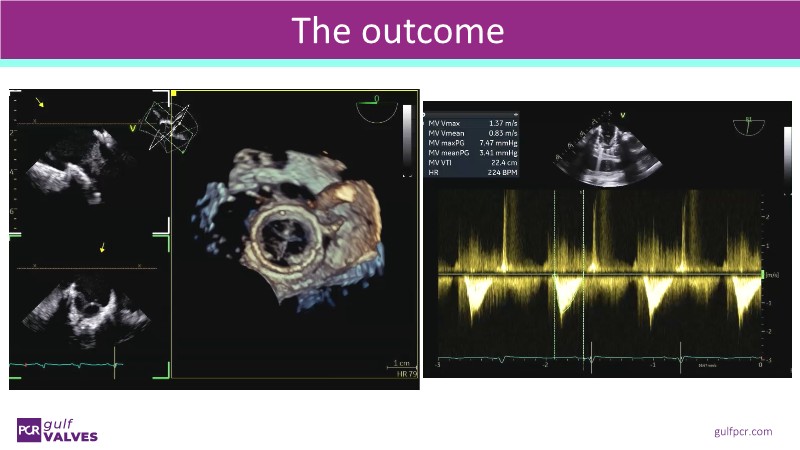

This session helps you anticipate and address complex scenarios such as mitral valve-in-valve, TAV-in-SAV, and valve-in-valve-in-valve procedures. Learn from expert case discussions that explore procedural strategies, technical challenges, and best practices to optimize outcomes in redo structural heart interventions.

- To anticipate and manage second valve scenarios with SAPIEN 3 Ultra RESILIA, including mitral valve-in-valve, TAV-in-SAV, and TAV-in-TAV